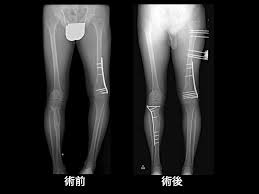

難治骨折診 帝京大学医学部 整形外科学講座